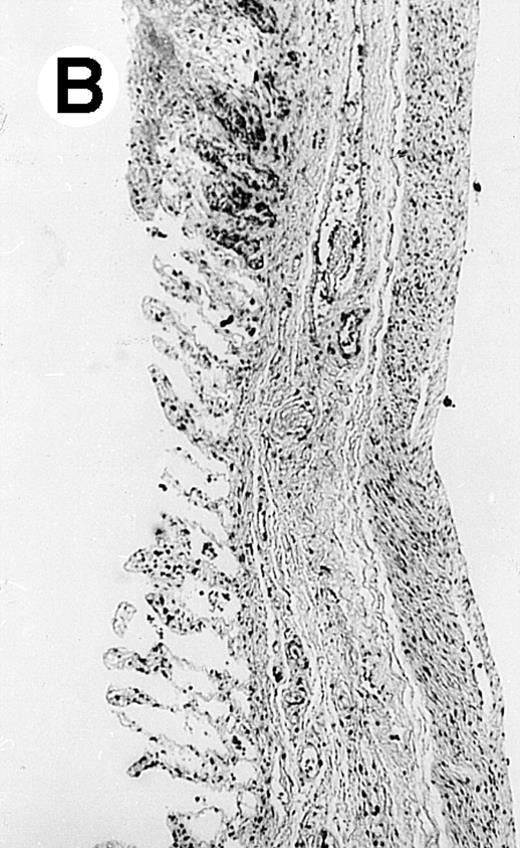

Pathologic findings in the small and large intestine were strikingly different depending on the treatment group. Figure 2A shows a representative pathologic sample from an animal assigned to the control group. Marked thinning of the bowel wall and extensive areas of epithelial cell sloughing was noted. Animals randomized to rhG-CSF treatment had minimal improvement in histologic findings with focal regions of preserved epithelium (Fig2B). Animals randomized to the rhIL-11 group showed substantial improvement with thickening of the epithelial layer and preservation of mucosal cell integrity (Fig 2C). Animals receiving both rhG-CSF and rhIL-11 had the most favorable histologic findings with normal mucosal thickness, minimal inflammatory changes, and preserved tissue architecture (Fig 2D). The composite analysis of the gastrointestinal pathology is provided in Table 1.

Histopathology of small intestinal mucosa cut in transection from an animal in each treatment group (study day 8). The upper panel (row 1) is a low power view (original magnification × 57); the lower panel (row 2) is a high power view (original magnification × 144). Note the diffuse thinning and necrosis of the mucosa with sloughing of intestinal epithelial cells in the control animal (A). There is progressive recovery of the thickness of the mucosa, reduction in inflammatory changes, and improved epithelial architecture with rhG-CSF (B), rhIL-11 (C), and combination therapy with rhG-CSF+IL-11 (D).